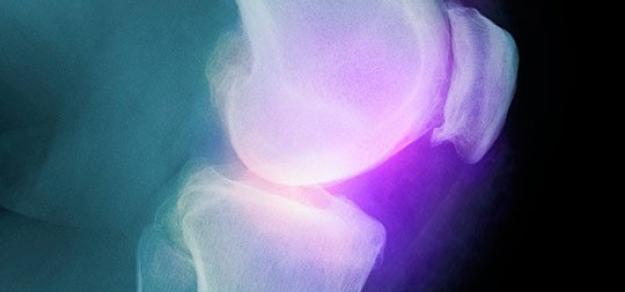

Cochrane Rev, 22 de mayo de 2017 Los autores tienen grandes reservas sobre los resultados debido a la participación de la industria farmacéutica y datos limitados. No se pudieron obtener los datos de tres estudios, que incluyeron 15.539 participantes, y se clasificaron como aguardando evaluación. La evidencia actual indica que el celecoxib es ligeramente mejor que el placebo y algunos AINEs para reducir el dolor y mejorar la función física, Esta mejora puede no ser clínicamente significativa